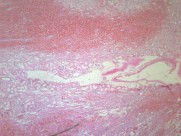

肾小管坏死(12)张

为急肾衰最常见类型,约占75%~80%.它是由于各种病因引起肾缺血及/或肾毒性损害导致肾功能急骤、进行性减退而出现的临床综合征.主要表现为肾小球滤过率明显降低所致的进行性氮质血症,以及肾小管重吸收和排泄功能低下所致的水、电解质和酸碱平衡失调.据尿量减少与否分少尿(无尿)…